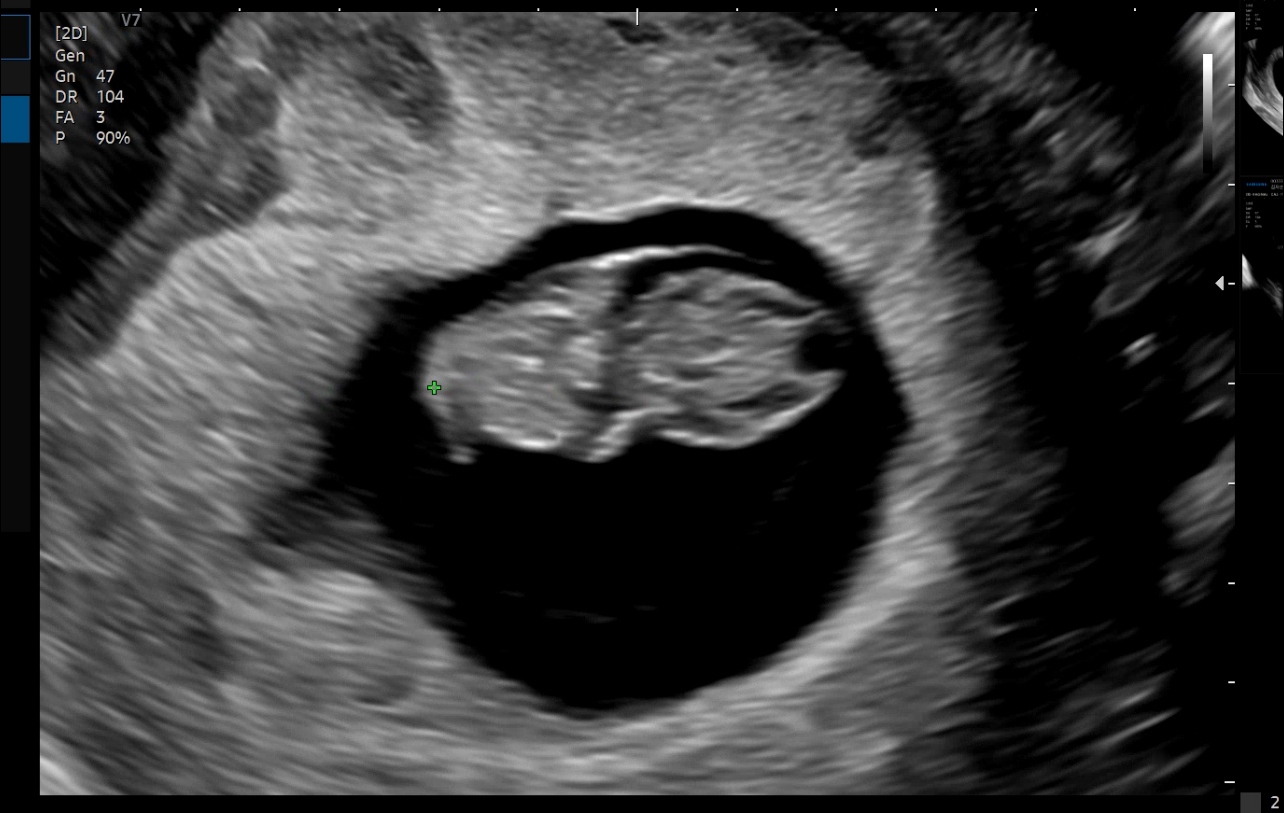

[2024.06.15] 두 번째 산부인과 방문 - 8주 5일차

첫 번째 산부인과를 방문하고 난 뒤 원래는 2주 후에 방문해야 하지만,오랑이가 일을 하고 있어 2주보다는 조금 늦게 대신 토요일 오전에 검진을 잡았다.  저번에는 평일날 방문해서 오랑이를 먼저 내려주고 10분 정도 기다리다 차도 세우고 그랬지만, 주말에는 차를 세우는 것 자체가 불가능했다. 저출산 국가라고 하면서 산부인과에 차와 사람들이 왜 이렇게 많은 거지??? 참 미스테리한 부분이다. 차는 기다리다가 병원에 주차하는 것을 포기하고 근처 마트에 세웠고 오랑이를 데리러 갔다. 오랑이 역시 병원 안에서 수많은 아이들과 산모들 사이에서 기다리고 있었다.  그렇게 같이 오랫동안 기달렸고 검사를 받으러 들어갔다.근데 왠지 모르게 우리 검사만 빨리 끝나는 느낌...저번과 동일하게 검사를 진행했는데 왕배가 몰라보게..